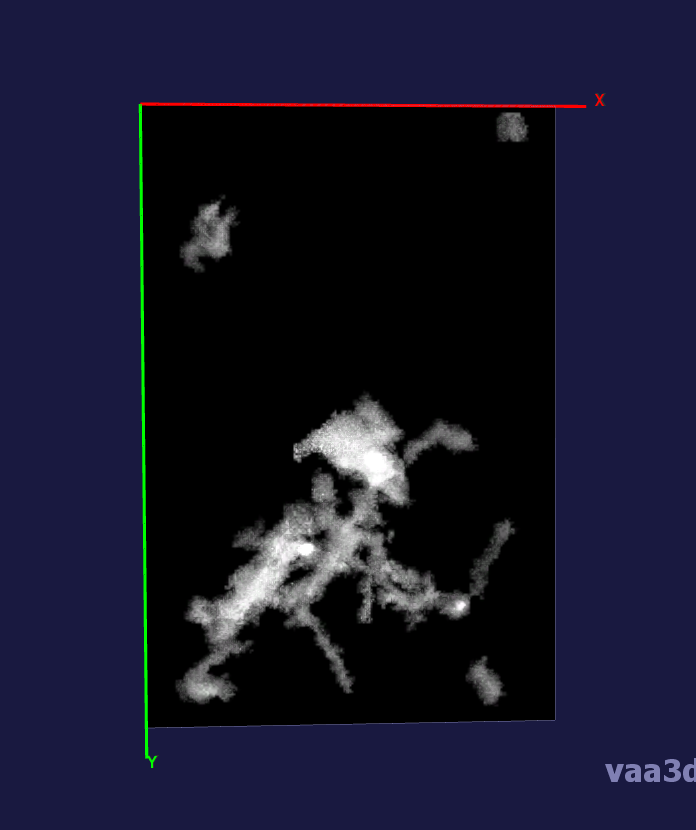

In our experiments, we compare the coupled TuFF-BFF microglia segmentation results with those given by L2S [21] and the Chan-Vese segmentation method [22]. The groundtruth in 3D was attained by manually tracing the object slice by slice from the z-stack. It must be noted that this was done by eye and could have some error. Figure 2 shows the visual comparison of the segmentation results for our dataset. Our result shown on the third column captures both the soma and processes. Figure 3 shows the Dice coefficient comparison of each segmentation method to the ground truth. Since the soma is much larger than the fine processes in the microglia, the processes have less volumetric impact on the similarity score. As explained in Section 1, segmenting the processes is important for quantifying the extension from the soma and its volume of surveillance. We use the Dice coefficient to quantitatively compare the ramification by taking the convex hull of the resulting segmentation. The Dice coefficient is a similarity measure that is computed using with where is the ground truth and is the compared image.

From Figure 4, the average Dice score for coupled TuFF-BFF was 0.77, compared to 0.53 for L2S [21] and .58 for Chan-Vese [22]. It must be noted that L2S required manual user initialization for each 2D image in the stack. While the Chan-Vese method has automatic seed selection, our coupled TuFF/BFF method was the only method that was a true 3D segmentation algorithm. L2S could not consistently capture the entire processes due to the intensity inhomogeneity throughout the object and background noise. The Chan-Vese segmentation could capture the extensions of the processes but did not work well with noise and attained false positives in the reconstruction. Since our method uses the tubular and blob information of the object to separate foreground and background, the segmentation only evolved within the object boundaries.